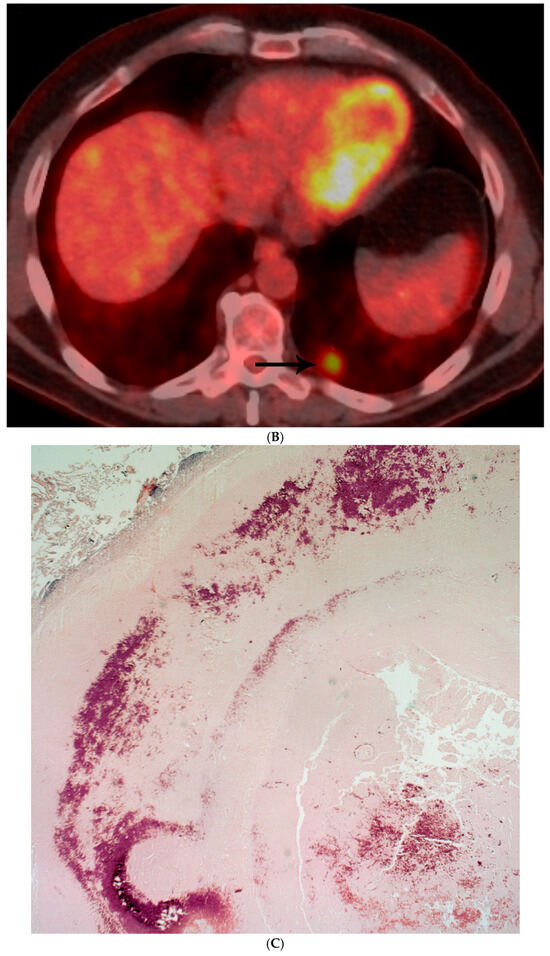

Coccidioidomycosis spp.: There were extensive areas of necrosis, and in conventional hematoxylin–eosin sections there were some fainted larger structures in some areas that on GMS stain showed the presence of large spherules with endospores morphologically in keeping with coccidioidomycosis (Figure 3A–D).

Figure 3.

(A) CT shows left lower lobe 4 cm solid mass (arrow) abutting major fissure with adenopathy (asterisks) in left hilar and subcarinal regions mimicking lung malignancy. (B) Mass shows enhancement with administration of intravenous contrast and measures 80 Hounsfield units with lobular irregular contour on CT with lung windows. (C) Large necrotizing nodule replacing lung parenchyma. (D) GMS shows numerous large spherules containing endospores morphologically compatible with Coccidioidomycosis spp.